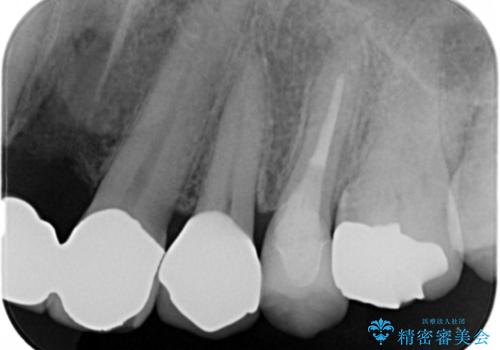

歯の表面の黒いところは虫歯ではなく

歯ブラシによる摩耗か歯ぎしりによるくさび状欠損によるものです。

そのままだと水などが染みてくる原因にもなります。

白い被せ物が入り希望に沿った処置となり

大変満足して頂けました。